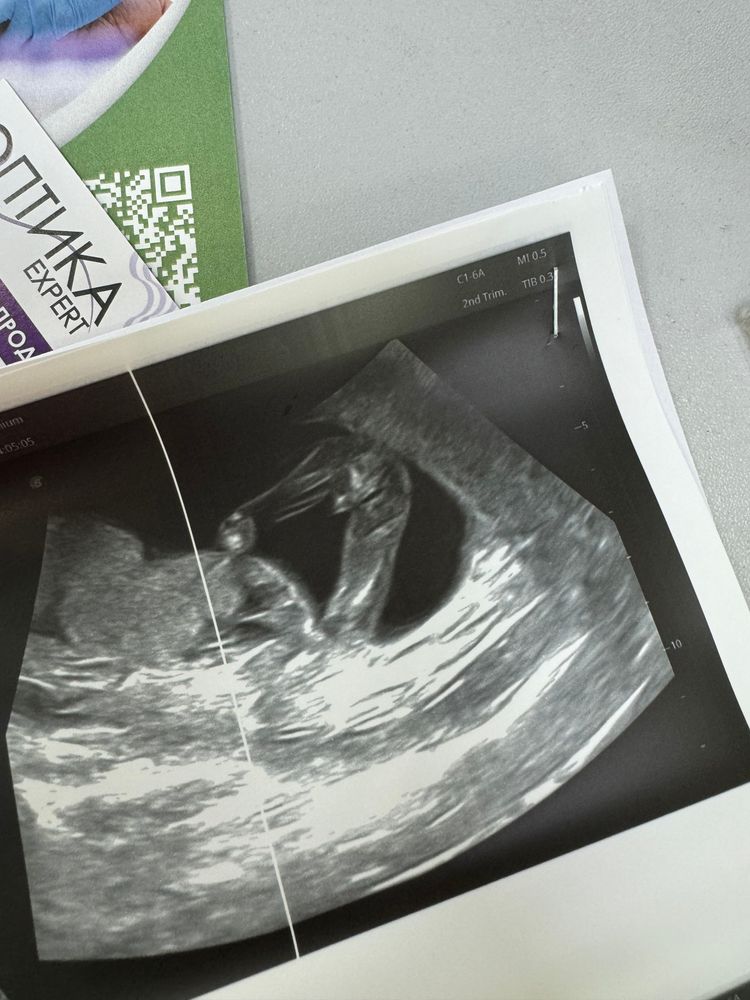

Всем привет. Такая ситуация, ходила в 16,3 недель на узи специально узнать пол ребенка, врач уверенно сказал мальчик, показал 3 раза мне все, и в заключении написал плод мужского пола. Я решила для достоверности пойти к другому через 3 дня, в 16,6 получается. Врач говорит никакого мальчика, тут девочка. Я ей говорю что вот мальчик был, она мне ответила что у нее 20 лет стажа , но на экране не выводила мне гениталии, поэтому я засомневалась. Первое фото типа девочка, второе типа-мальчик

Маргарита

Натали , на всех.

на верхних ничего не торчит,на нижнем две полоски и пуповина.

но точно видно только врачу